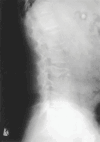

Musculoskeletal tuberculosis (TB) accounts for approximately 10% of all extrapulmonary TB cases in the United States and is the third most common site of extrapulmonary TB after pleural and lymphatic disease. Vertebral involvement (tuberculous spondylitis, or Pott's disease) is the most common type of skeletal TB, accounting for about half of all cases of musculoskeletal TB. The presentation of musculoskeletal TB may be insidious over a long period and the diagnosis may be elusive and delayed, as TB may not be the initial consideration in the differential diagnosis. Concomitant pulmonary involvement may not be present, thus confusing the diagnosis even further. Early diagnosis of bone and joint disease is important to minimize the risk of deformity and enhance outcome. The introduction of newer imaging modalities, including MRI (imaging procedure of choice) and CT, has enhanced the diagnostic evaluation of patients with musculoskeletal TB and for directed biopsies of affected areas of the musculoskeletal system. Obtaining appropriate specimens for culture and other diagnostic tests is essential to establish a definitive diagnosis and recover M. tuberculosis for susceptibility testing. A total of 6 to 9 months of a rifampin-based regimen, like treatment of pulmonary TB, is recommended for the treatment of drug susceptible musculoskeletal disease. Randomized trials of tuberculous spondylitis have demonstrated that such regimens are efficacious. These data and those from the treatment of pulmonary TB have been extrapolated to form the basis of treatment regimen recommendations for other forms of musculoskeletal TB.